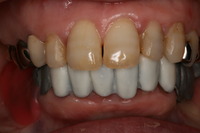

前歯の白い部分は仕上がりをイメージして、ワックスで仮に仕上げてあります。

この入れ歯は、奥歯のほとんどの部分を白く仕上げる予定です。

白い部分は、陶材(ポーセレン)を焼き付けて美しく仕上げる予定です。

リーゲルレバーを閉じたところです。

お口にしっかりと固定され、びくともせずにしっかりと咬むことが出来ます。